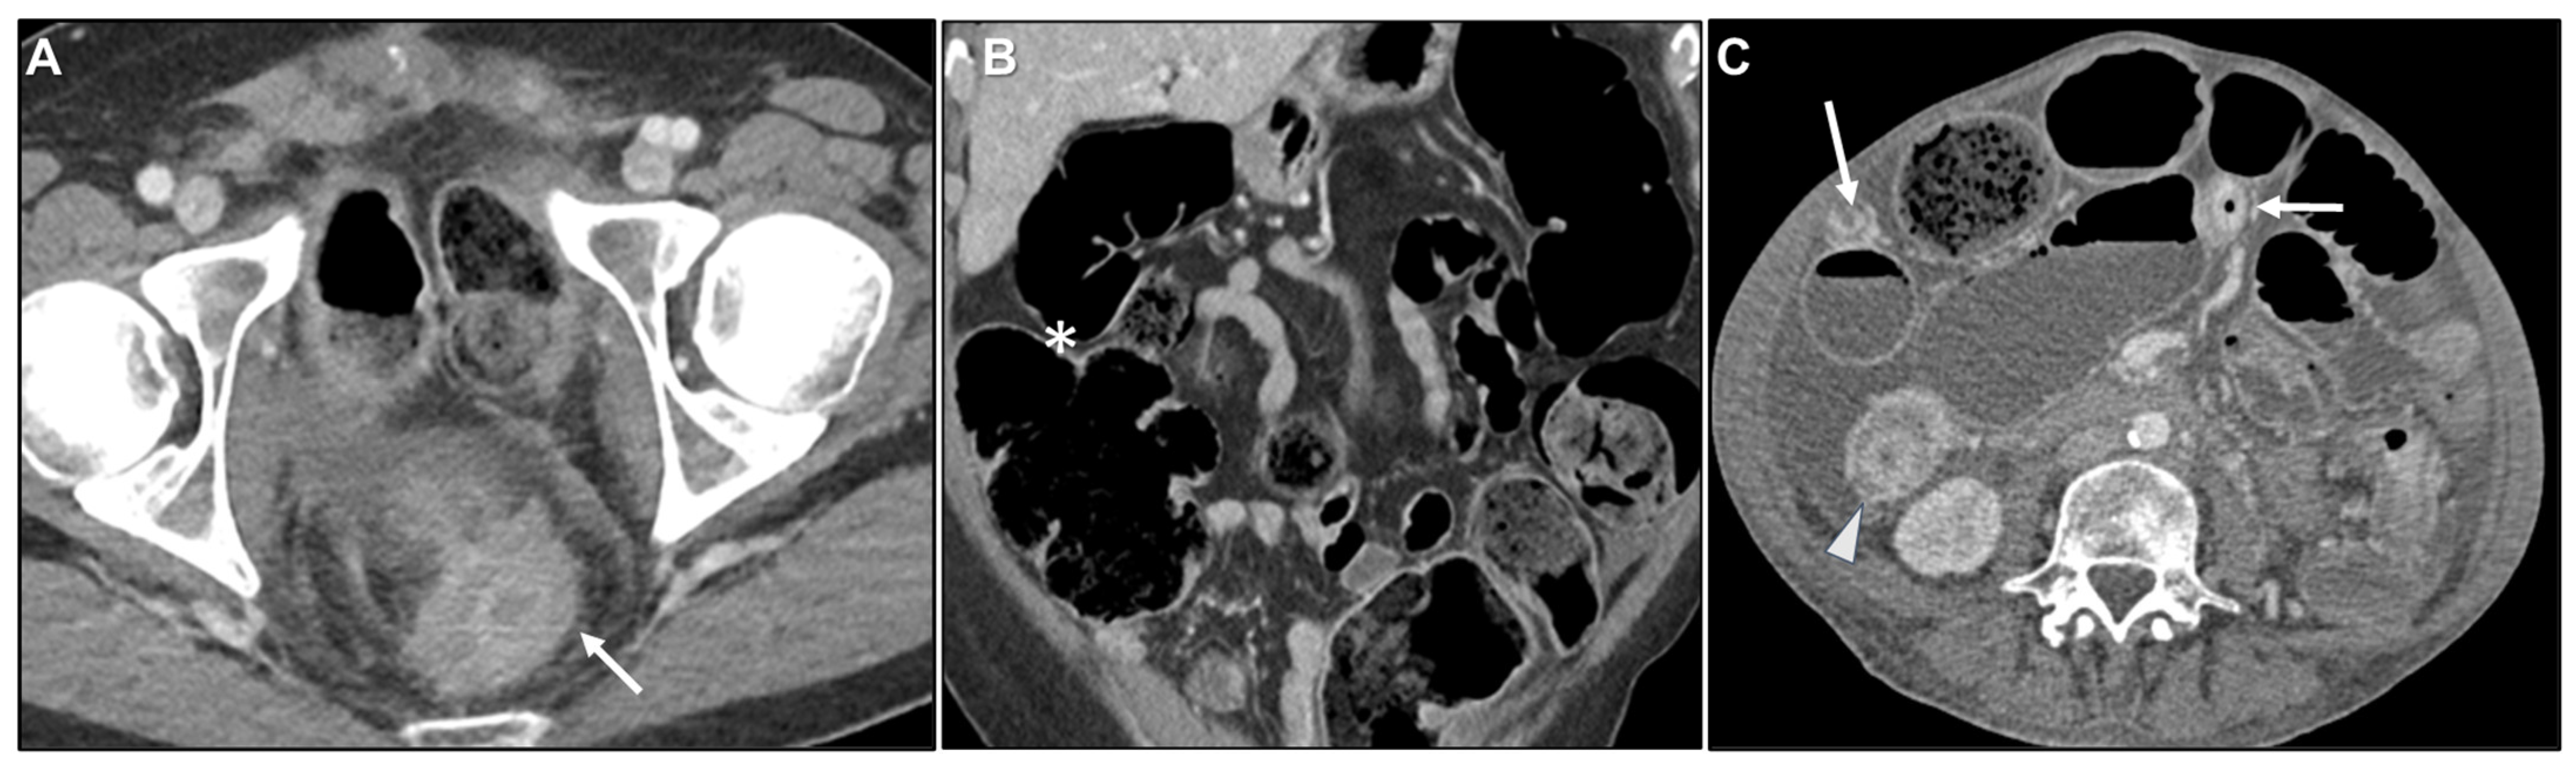

Intestinal Obstruction

Peritoneal Carcinomatosis